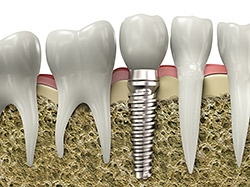

An implant is a synthetic tooth root in the shape of a post that is surgically placed into the jawbone. The “root” is usually made of titanium: the same material used in many replacement hips and knees, and a metal that is well-suited to pairing with human bone. A replacement tooth is then fixed to the post. The tooth can be either permanently attached or removable. Permanent teeth are more stable and feel more like natural teeth.

If you’ve lost a tooth, your dentist may have recommended getting a dental implant to fill the empty space and allow for optimal function of your teeth. The dental implant itself is only a replacement for the root of the lost tooth, so after the implant has been placed, you’ll still need to get a restoration, or replacement tooth. Implants provide a strong foundation for fixed (permanent) or removable replacement teeth that are made to match your natural teeth.

To make the new tooth or teeth, your dentist will make an impression of your existing teeth, creating a model of your bite. The new restoration, most typically a crown, will be based on this model so it will blend in perfectly with the rest of your teeth. The crown is then attached to the connector point (abutment) on your implant.